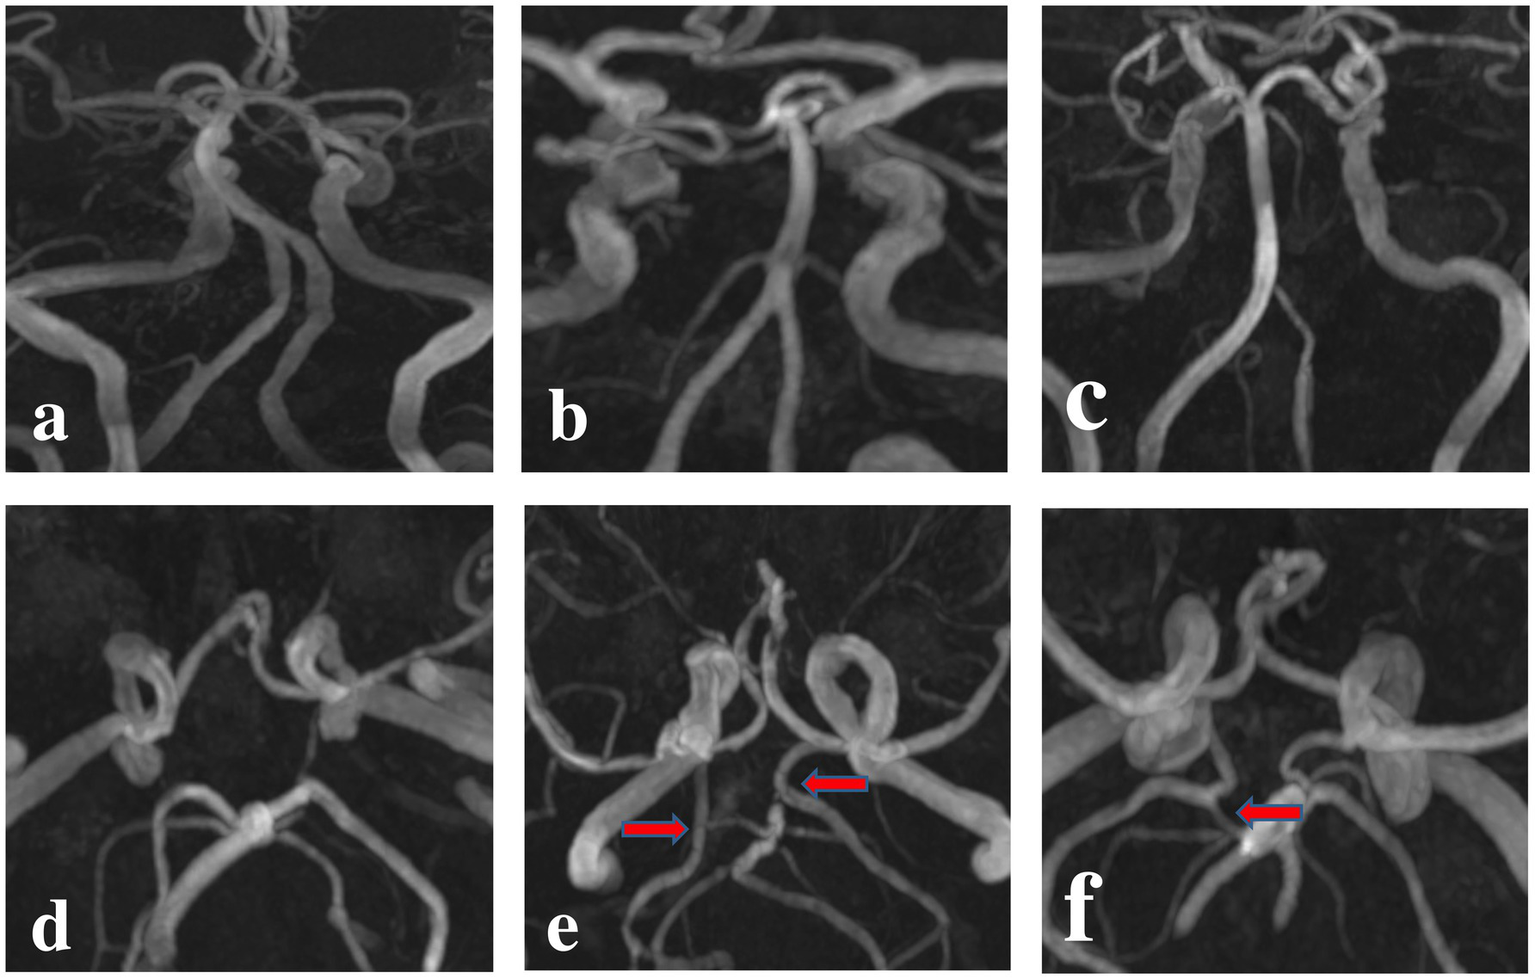

3D TOF-MRA was used to determine the vertebral artery anatomies and PCA variation. The anatomical configuration of the vertebrobasilar artery included three geometries (15). Walking geometry refers to the bilateral vertebral arteries have similar diameters (<0.3 mm) and coverage in same bending direction to form BA; Tuning fork geometry refers to the bilateral vertebral arteries have similar diameters (<0.3 mm) and coverage in opposite bending direction to form BA; Lambda geometry refers to the bilateral vertebral arteries have different diameters (≥0.3 mm) to form BA. The PCA morphology included three geometries. Normal PCA refers to the vessel outer diameter of P1 segment is larger than the ipsilateral posterior communicating artery (PcoA), with a PcoA/P1 < 1, and its blood mainly originates from BA system; CFTP refers to the P1segment is disappeared, and its blood is all from the ipsilateral internal carotid artery (ICA); PFTP means that the P1 segment is visible on MRI, but the outer diameter of P1 segment is significantly smaller than the ipsilateral PcoA, with a 1 < PcoA/P1 < 1.5, and its blood mostly comes from the ipsilateral ICA (9, 16). It was shown in Figure 1.

Figure 1

Anatomical morphology of the vertebral artery and PCA on 3D TOF-MRA: the morphology of vertebral artery was categorized as Walking (A), Tuning Fork (B) and Lambda (C) Geometries according to the diameter difference and bend direction in bilateral vertebral artery. The morphology of PCA was categorized as normal PCA (D), CFTP (E) and PFTP (F) according to the development of PI segment.